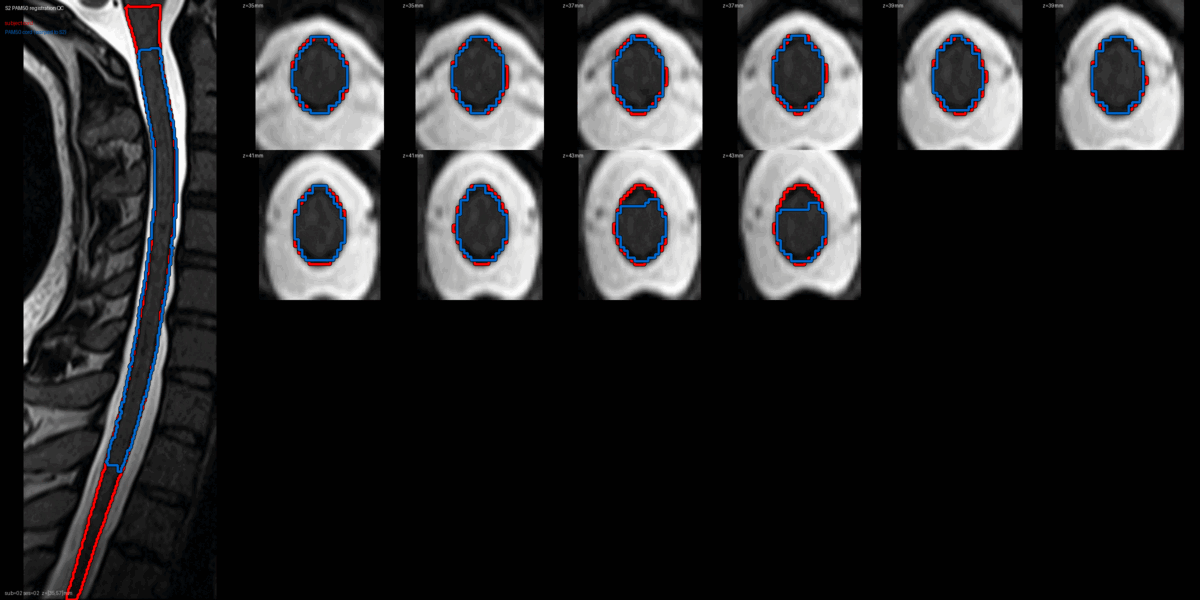

QC: PAM50 Registration Overlay

This animated GIF alternates between subject anatomy and template overlay.

What to look for:

- ✅ Cord contours align between subject and template

- ✅ No large rotational offsets

- ❌ FAIL: Significant misalignment (>5mm offset)